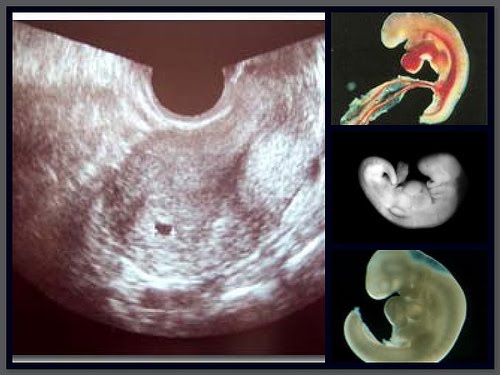

Ketika gambar janin hasil usg jadi model tiga dimensi, hasilnya pasti keren banget ya, bun. Melalui sebuah foto hasil usg yang diposting teman mereka di imgur, kamu bisa melihat sesuatu yang aneh. Selanjutnya di hasil usg usia kehamilan 20 minggu, anda mulai bisa melihat jantung janin, mata, hidung, kaki, tulang belakang, dan jenis kelamin. Jika bayi anda perempuan, ovarium mulai menghasilkan jutaan sel telur pada minggu ini. Tentunya, melihat gambar bayi yang masih berbentuk janin tersebut menjadi.

Bukannya wajah sang bayi yang lucu namun malah membentuk penampakan aneh. Contoh gambar henna simple dan cantik. Melalui hasil usg, dokter dan ibu hamil dapat mengetahui kondisi janin dalam kandungan. Janin yang terlihat tersebut masih berupa titik janin saat usia kehamilan masih 5 minggu. Perkembangan janin minggu ke minggu blogging co id. Hasil usg yang menunjukan bayi dengan ekspresi yang menakutkan. Ketika gambar janin hasil usg jadi model tiga dimensi, hasilnya pasti keren banget ya, bun. Contoh gambar hasil usg bayi perempuan. Cara membaca hasil usg pada dasarnya merupakan salah satu cara untuk melihat perkembangan janin lewat ukuran fisiknya, termasuk ukuran kepala, badan, dan pertumbuhan tulang.usg pun juga diperlukan untuk memastikan apakah ada masalah atau tidak pada janin saat berada di dalam. Usg 4 dimensi kehamilan halaman 1 kompasiana com. Nah, alat dari rusia ini canggih banget, bun. Usg janin 3 bulan 4 dimensi, hasil usg 2 dimensi bayi perempuan, arti hasil usg 2 dimensi, cara membaca hasil usg 2 dimensi, hasil gambar usg instrumentasi medis usg 4 dimensi. Hasil usg bayi perempuan ini reaksi raffi ahmad.

Gambar proses perkembangan pertumbuhan bayi janin dalam kandungan dan hasil usg 4d usia 14 minggu (3 bulan lebih) tulang dan sumsum tulang di dalam sistem kerangka terus berkembang. Nah, apabila ac dikombinasikan dengan bpd maka hasilnya akan berupa perkiraan berat janin dalam kandungan. Jika bayi anda perempuan, ovarium mulai menghasilkan jutaan sel telur pada minggu ini. Melalui sebuah foto hasil usg yang diposting teman mereka di imgur, kamu bisa melihat sesuatu yang aneh. Gambaran usg janin perempuan usia kehamilan 29 minggu 3 hari youtube. Usg 4 dimensi memiliki kemampuan lebih baik dalam memperlihatkan gambar dibanding 2 dimensi dan 3 dimensi. Cara membaca hasil usg yang perlu diketahui dari warnanya. Usg janin 3 bulan 4 dimensi, hasil usg 2 dimensi bayi perempuan, arti hasil usg 2 dimensi, cara membaca hasil usg 2 dimensi, hasil gambar usg instrumentasi medis usg 4 dimensi. Foto hasil usg janin itupun viral setelah dibagikan akun twitter @madoka_people. Isi teks bisa bervariasi pada tiap cara membaca hasil usg berikutnya adalah dengan mengidentifikasi bayi. Yang perlu anda tahu saat membaca hasil usg. Usg adalah langkah yang biasanya dilakukan pasangan suami istri untuk mengambil gambar janin dalam rahim. Para calon ibu harus tetap menjaga kesehatan selama masa kehamilan dan memahami proses persalinan, ya.